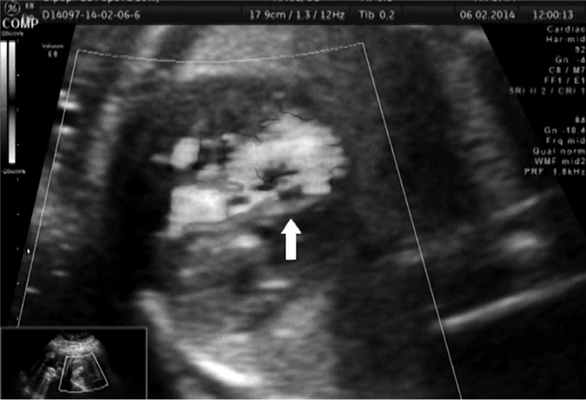

В сроке 27—28 нед беременности сформировалась ГЛОС с рестриктивным * овальным окном (рис. 2). После проведения перинатального консилиума пациентке была предложена вальвулопластика овального окна.

Рис. 2. Пациентка П., 27—28 нед беременности. ГЛОС с рестриктивным овальным окном.